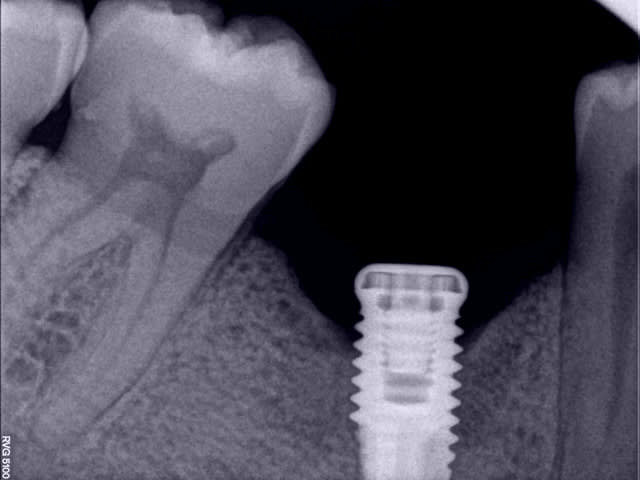

Une perte osseuse non infectée n'est pas une périimplantite et elle se stabilise à un certain niveau lorsque le système est en bio-équilibre.

Ici, il est dommage que l'implant soit un peu court, ce qui peut entrainer sa perte par surcharge.

Je ne pense pas que ce soit une périimplantite et le tabac n’est pas la cause de la perte osseuse mais un facteur aggravant.

bonsoir, ci dessous quelques réflexions personnelles sur cette péri-implantite

Par ailleurs, un axiom se pose effectivement en infra osseux d'1/2mm mini, et à priori, il y avait vraiment la place pour le faire. Les conséquences auraient été un peu "moindres" s'il avait été posé de cette manière. Maintenant, ça arrive à tout le monde de ne pas faire la pose parfaite, ça m'est arrivé à moi aussi évidemment.

A part ça, la péri-implantite fait malheureusement partie du jeu et il est parfois très difficile d'expliquer sa venue.

Dans ton cas, si ton implant n'est pas mobile, je le garderai après curetage soigneux sous aide visuelle et décontamination par aeropolissage et bétadine, et ensuite, comblement et membrane avec suture sans tension et couverture AB.

Ce qui me chagrine dans une dépose, s'il est encore fixe bien sûr, c'est que tu risque d'aggraver la perte osseuse existante et de créer un cratère entre la 5 et la 7, ce qui va peut-être compliquer la maintenance paro après la pose de la couronne, ou l'esthétique de la couronne.